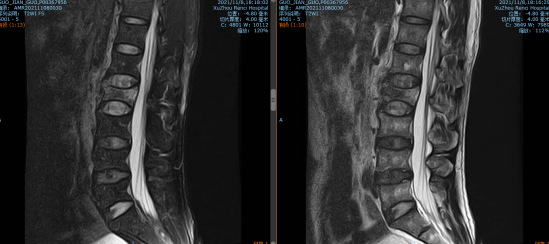

11月初山东的郭大叔如往常一样在厂里干活,突然设备掉落砸伤了其腰背部,当时他就不能动了,家人、同事连忙将他送到当地医院检查,结果ct显示大叔的L2椎体骨折。这可急坏了大叔的家人,家人找亲朋好友四处打听,得知betway在线登陆可以做脊柱微创手术,连夜带着郭大叔来我院就诊。

脊柱科孟磊副主任医师为大叔检查后,发现他不单单是腰椎骨折,还有胸骨体骨折、腰椎横突骨折、棘突骨折、右侧第3-5、8肋骨骨折伴有肺部挫伤以及胸腔积液。患者家属表示,大叔是家中的主要劳动力,请求孟医生一定要帮帮他们一家!孟医生手术团队决定采用机器人辅助下腰椎骨折复位内固定术。和传统手术相比,天玑骨科机器人辅助更安全高效,手术切口小、定位精确无误差、伤口小、疼痛轻、恢复快。

最终,孟磊副主任医师团队在天玑骨科机器人定位下,通过3D图像扫描规划手术中椎弓根螺钉的进钉点、置钉方向以及置钉深度。根据机器人系统导航,通过机械臂精准定位置钉位置,医生只在置钉部位切开约2cm切口,不损伤其它椎关节,保障神经安全和手术的有效性。